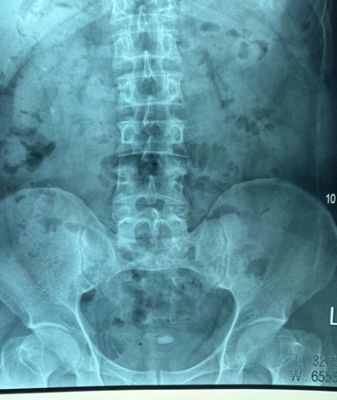

+ Phim XQ hệ tiết niệu không chuẩn bị (KUB): 2 thận không có sỏi. Nốt cản quang ở vùng tiểu khung hơi lệch trái kích thước 20 x 10 mm, đậm độ cản quang cao.

Hình 2: KUB, hình ảnh sỏi cản quang ở tiểu khung, lệch trái